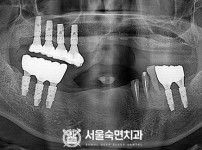

임플란트-전후사진2